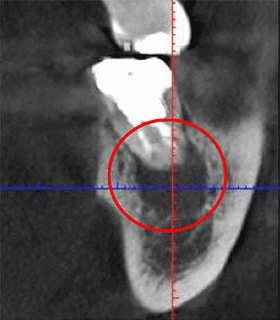

治療の道具について説明をする前に、「根管」の画像をご覧ください。黒く見えるところが根管です。

ご覧の通り根管は非常に複雑な形をしていて、患者さんごとに形が異なります。また、歯の中のことですから非常に細く、もっとも狭いところは直径1㎜もありません。

下の画像は、CTとレントゲンで同じ患部を撮影し、比較したものです。

左がCT、右がレントゲンです。

左の画像では赤い丸の中に、黒い影が見えます。しかし、右の画像にはありません。この影の正体は、神経の炎症です。もしもレントゲンだけで検査をしていたら、この炎症には気が付かないまま治療を終えてしまったかもしれません。

初期の小さな炎症も見逃さず、適切に治療を進めるには、CTでの画像診断が欠かせないのです。